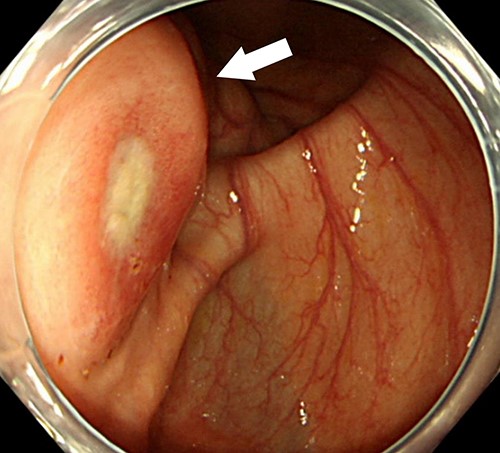

A 74-year-old female with hypertension, hyperlipidemia and hyperuricemia had a colonoscopy as a screening examination. The colonoscopy revealed an extrinsic compression with ulceration located at the cecum (Fig. 1). A multidetector computed tomography (CT) identified a low-attenuation distorted cystic lesion with focal calcification in the anatomic region of the right iliac fossa, measuring 6.1 × 5.0 × 3.7 cm (Fig. 2). Findings from the routine laboratory examinations were unremarkable, and all tumor markers were within normal range. The patient was scheduled for ileocecal resection with lymph node dissection due to the possibility of malignancy, such as appendiceal mucinous adenocarcinoma, because of the large and distorted tumor. Contrast-enhanced CT was conducted for further assessment of the findings, and we found that the cystic lesion was dramatically shrinking. It seemed improbable that rupture of the tumor had happened since no findings implied the spread of mucinous components, such as ascites or mucinous peritoneal nodules on CT. It was considered that the mucinous content was spontaneously drained from the root of the appendix to the cecum. However, the enhanced and distorted lesion with focal calcification, suggesting malignancy, had remained in concordance with the base of appendix (2.7 × 2.1 × 1.9 cm) (Fig. 3). Therefore, ileocecal resection was performed as planned, and laparoscopic procedure was selected due to the unlikelihood of the tumor rupturing. The base of appendix was distended and there were no obvious peritoneal anomalies upon visualization of the abdomen (Fig. 4). The specimen was handled with care and there was no spillage of cystic contents. The post-operative course was uneventful, and the patient was discharged on post-operative day 8.

Colonoscopy examination showing an extrinsic compression with ulceration located at the cecum (arrow).